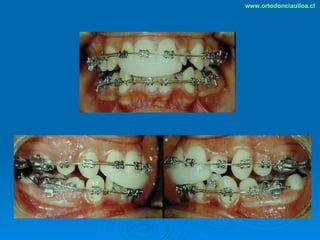

Este documento presenta dos casos clínicos de pacientes que recibieron tratamiento de ortodoncia. El primer caso fue de una paciente femenina de 14 años con apiñamiento dental y mordida cruzada que fue tratada mediante extracción de premolares y alineamiento dental. El segundo caso fue de un paciente masculino de 14 años con clase II esqueletal y desarmonía dentomaxilar que fue tratado con extracción de premolares y corrección de mordida. Ambos casos mostraron mejoría después de 3 años de tratamiento.